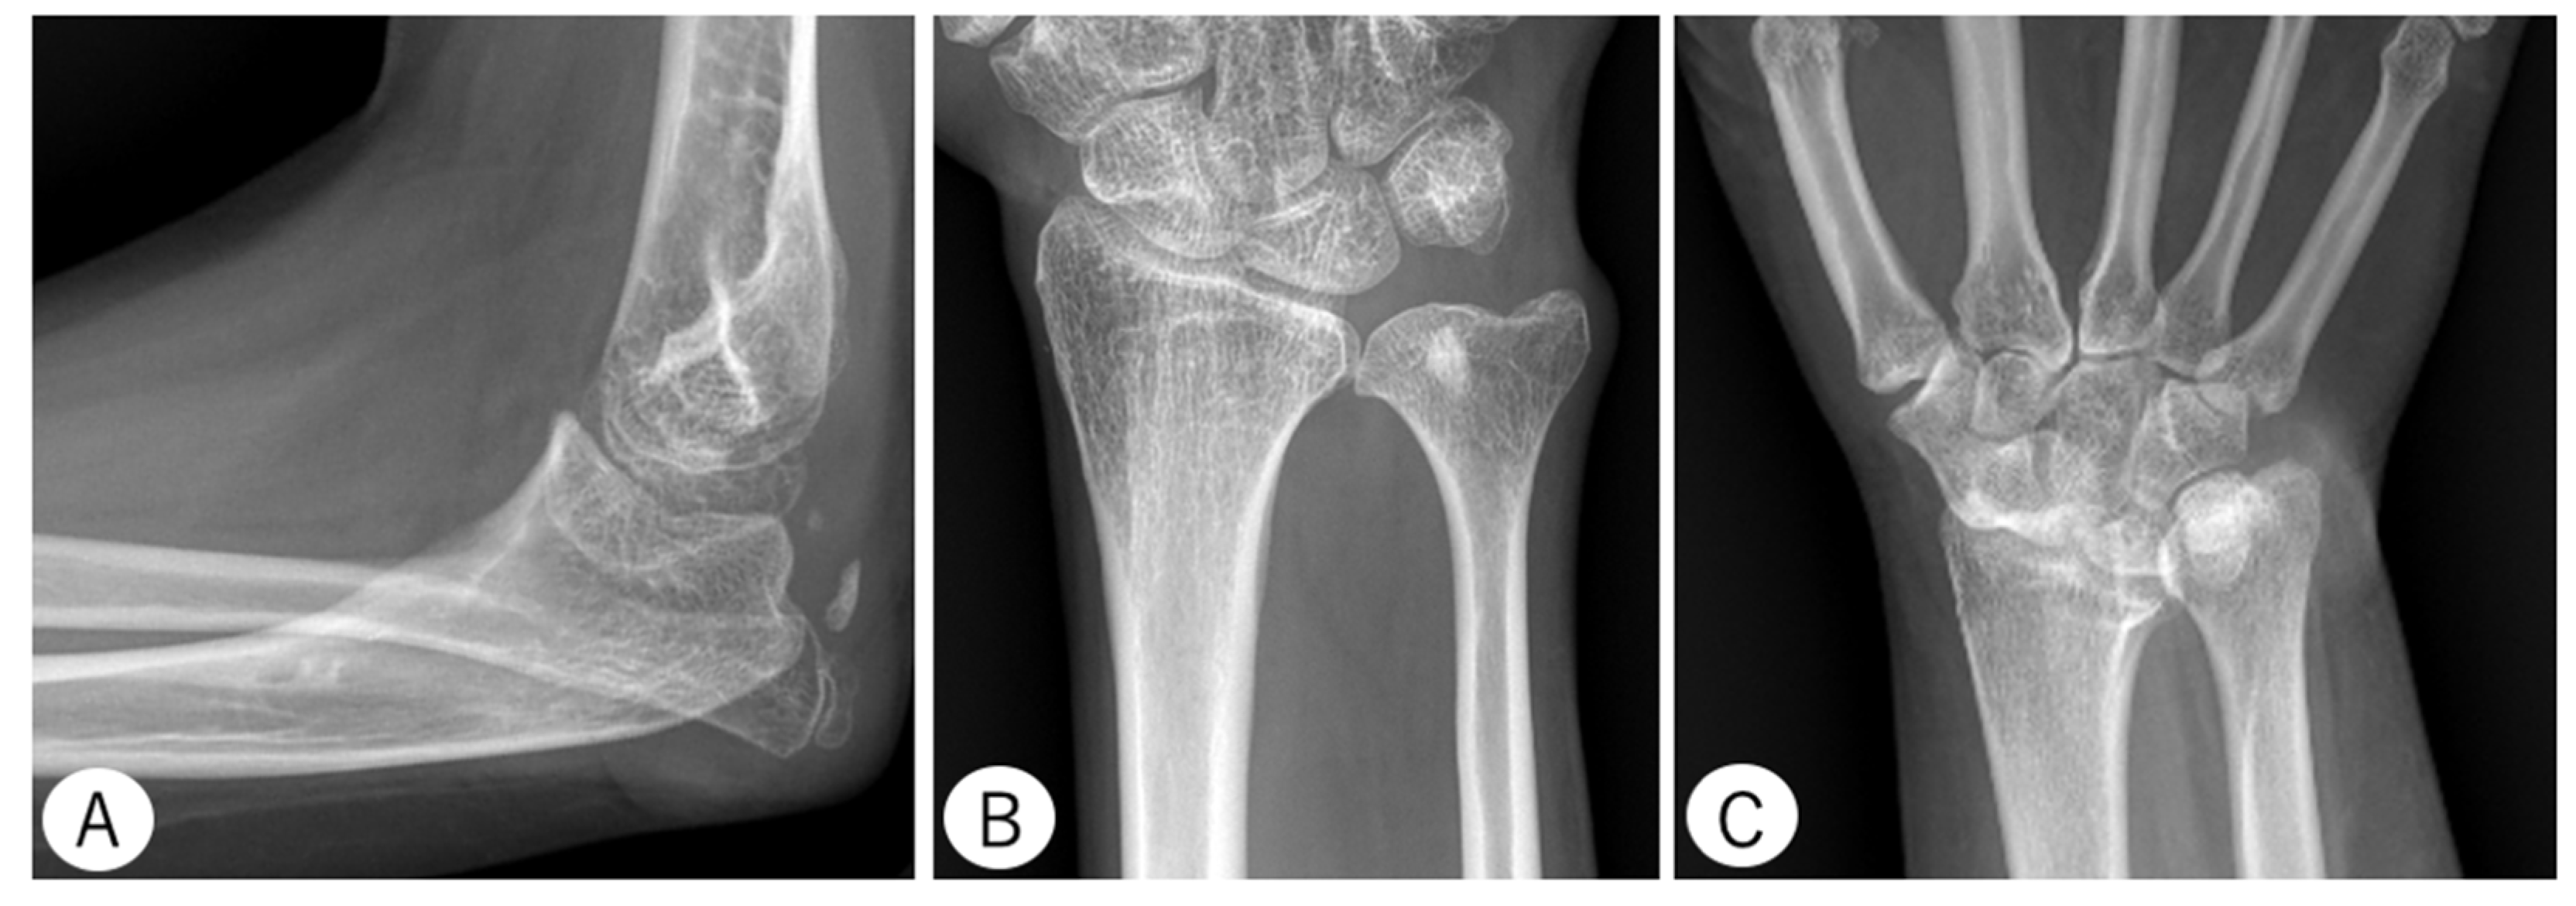

2.3.1. Elbow

- Anterior Coverage Index (ACI): defined as the ratio between the coronoid height (point A to B) and the minimal proximal ulna trochlear height (C to D).

- Trochlear Depth Index (TDI): defined as the ratio between the proximal ulna trochlear notch depth (F to G) and olecranon–coronoid distance (A to E).

- Proximal Ulnar Bow (PUB): defined as the angle between the ulnar diaphysis and olecranon.

- Radiographic Opening Angle (ROA): defined as the angle between lines from the deepest point of the trochlear notch to coronoid (A to G) and olecranon (G to E).